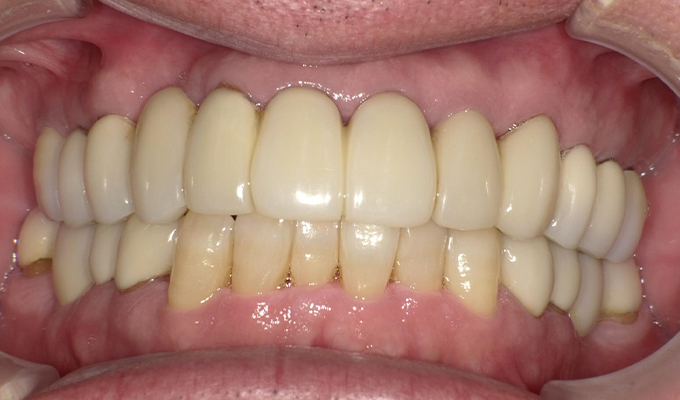

case5インプラント+メタルボンドブリッジ

初診時(2010年)

初回メンテナンス時(2012年)

最新メンテナンス時(2023年)

- 初診時の年齢

- 40代女性 (2010年)

- 主訴

- 5年ほど前に上に総入れ歯を作った。(マグネットタイプ)食事してたら人口歯が取れてしまった。インプラントに興味がある。40代なので入れ歯はやっぱり嫌、とのことでした。

- 治療内容

- 上・・・虫歯の根だけの歯が数本残っているためすべて抜歯し仮義歯作成しました。最終的には8本インプラントを埋入し上部構造はメタルボンドです。

下・・・保存できる下の歯はメタルボンドブリッジにし、奥歯のない部分に3本インプラントを埋入しました。治療期間は2年ほどかかりましたがしっかり食事ができるようになったので嬉しいと、満足していただけました。

以降定期的にメンテナンスに来院いただき11年経過してもいい状態を維持されています。